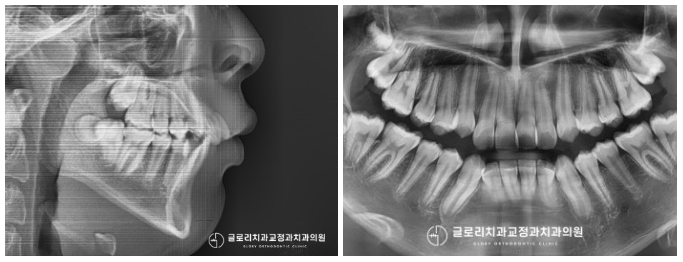

중랑구 교정치과 검진 결과 심한 총생과

틀어져 있는 앞니가 눈에 띄었는데요.

송곳니는 배열 밖으로 벗어나

덧니와 같은 모습을 갖고 있었으며,

상악 전치부 치아는 전방으로 튀어나와 있는 것을

확인할 수 있었습니다.

이분의 경우 좁은 악궁이 문제라는 판단이 들었는데요.

자라야 될 이의 개수는 정해져 있지만

맹출 공간은 좁은 편에 속해 생기게 된 문제입니다.